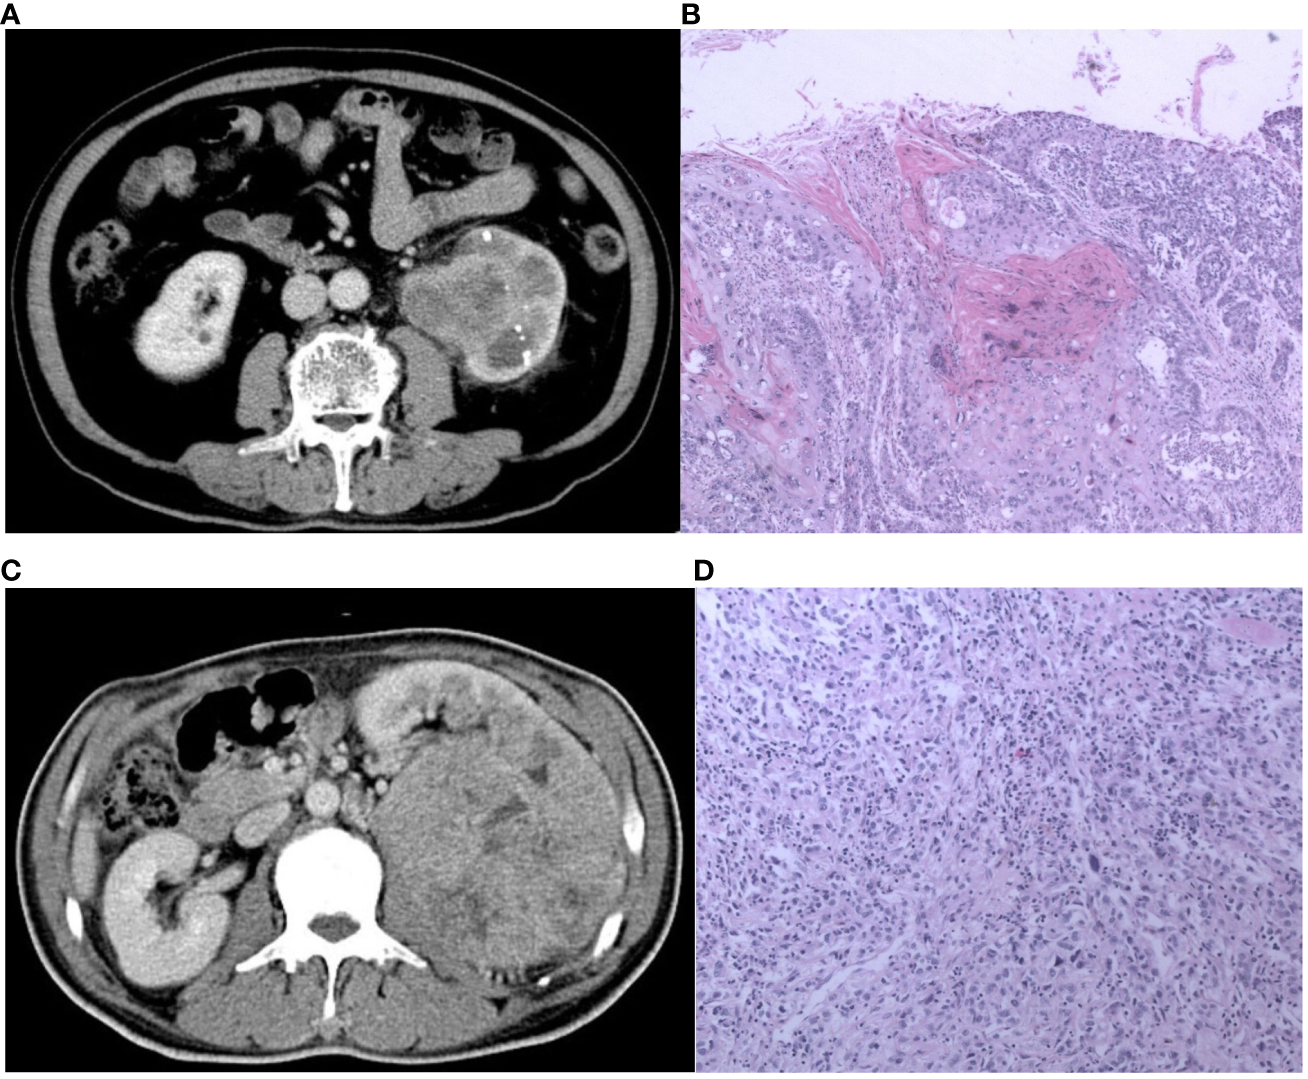

Figure 5 The CT and pathological images of the pyelocaliceal upper urinary tract urothelial carcinoma and infiltrative renal cell carcinoma. (A) A 60-year-old man with left kidney stones, hematuria, and left waist soreness. CT images show enlarged volume of the left kidney, multiple high-density nodular shadows in the parenchyma, and obvious expansion of the left renal pelvis with blurred edges, heterogeneous enhancement, and unclear boundary. (B) Pathological images (H&E, ×100) showed an invasive urothelial carcinoma infiltrating the muscle layer of the renal pelvis and infiltrating the renal parenchyma and finally diagnosed as pyelocaliceal upper urinary tract urothelial carcinoma, which was consistent with the judgment of nomogram. (C) A 56-year-old man with lower back pain and hematuria for more than 3 months. CT image showed a huge soft tissue mass in the left kidney, with heterogeneous enhancement, unclear boundaries, a low-density filling defect in the left renal vein, and an enlarged lymph node in the left retroperitoneum. (D) Pathological images (HE, 100×) showed a transparent cell carcinoma of grade 3 with necrosis, invading the renal capsule, renal pelvis mucosa, and renal sinus fat, and it was finally diagnosed as infiltrative RCC, which was not consistent with the judgment of nomogram.